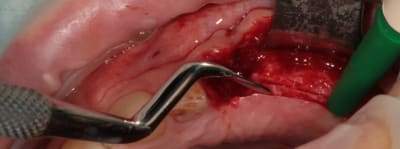

5:

évolution il faut obtenir de quoi placer un diamètre 3,4

de nouveau lame 15 pour incision de décharge verticale

6

lame 15

manuel et impacté au maillet (cool)